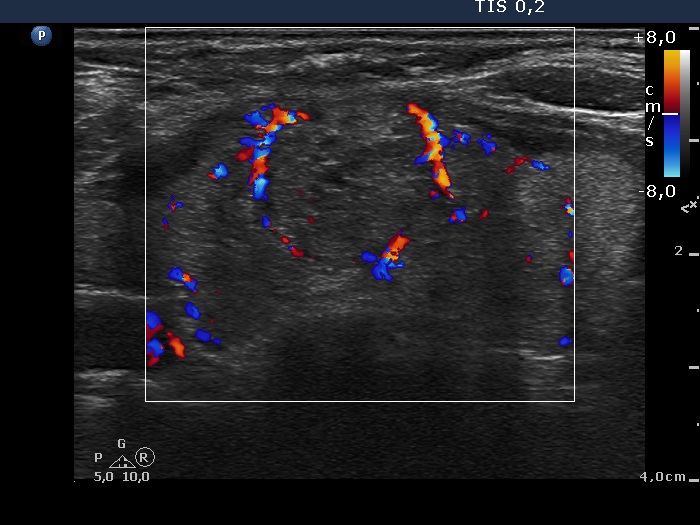

Ultrasonography. The thyroid was echonormal and had a small hypoechogenic lesion in the ventrolateral part of the right lobe. There was a hyperechogenic nodule having coarse calcification in the isthmus while the left lobe also had discrete lesions.